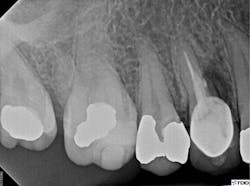

A clinical exam confirmed the presence of a draining sinus tract. Periodontal

probing depths were within normal limits, and the restoration was intact. The radiograph showed previous root canal therapy, post, and crown. A radiographic exam revealed a radiolucent area on the mesial aspect of tooth No. 5 in the coronal third adjacent to the post, as well as a periradicular radiolucency (figure 1).

Figure 1: Radiolucent area on mesial aspect of tooth No. 5 in coronal third adjacent to post, as well as a periradicular radiolucency